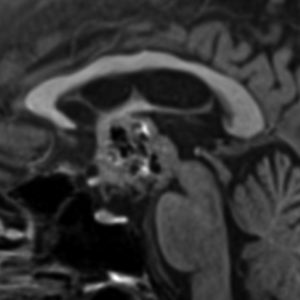

1968年 18歳の時に頭痛嘔吐で発症しました。第3脳室腫瘍と閉塞性水頭症の診断だけで,シャント手術を受けました。手術も化学療法も放射線治療もされていません。下の画像は60代で撮影されたものです。この例では,第3脳室内に増大した大きな毛様細胞性星細胞腫が,視床下部下垂体障害を出すことなく,自然経過で増大停止 growth arrest して,カチカチに固まってしまうということを教えてくれます。でも,こんなに都合よく経過観察できる例も珍しいです。

CTでは強い石灰化があります。右のT2強調画像では腫瘍は等信号,視交叉の後ろにあります。内部の低信号は石灰化です。

T1強調画像では等信号,ガドリニウム増強でごく一部がまだらに増強されます。